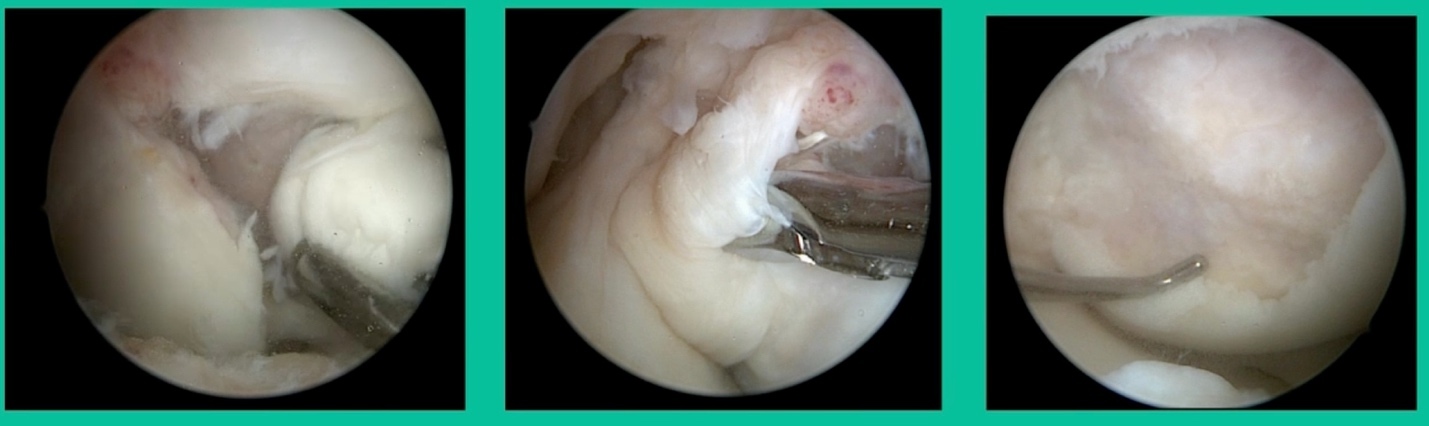

This is another one. 17-year-old basketball player (Figure 5).

Oddly, this patient had posterior knee pain. I gave him a lidocaine injection because I couldn’t figure out what was going on. He got relief and I said, “Look, something’s going on in the joint. The only thing you got is this trochlear thing.” It was a piece of cartilage. This is all it was.

You can actually, in a young person, get cartilage to heal with no bone on it, and we use compression suture fixation (Figure 6). In his follow-up, five months after undergoing suture fixation of lateral trochlear OCD, he had a little squeaking in the knee because of the sutures there. That actually went away in time. Maybe the sutures ruptured. But he had a squeaking knee for about three months, and then that went away. So, you can fix an all-cartilage problem using a suture compression technique.